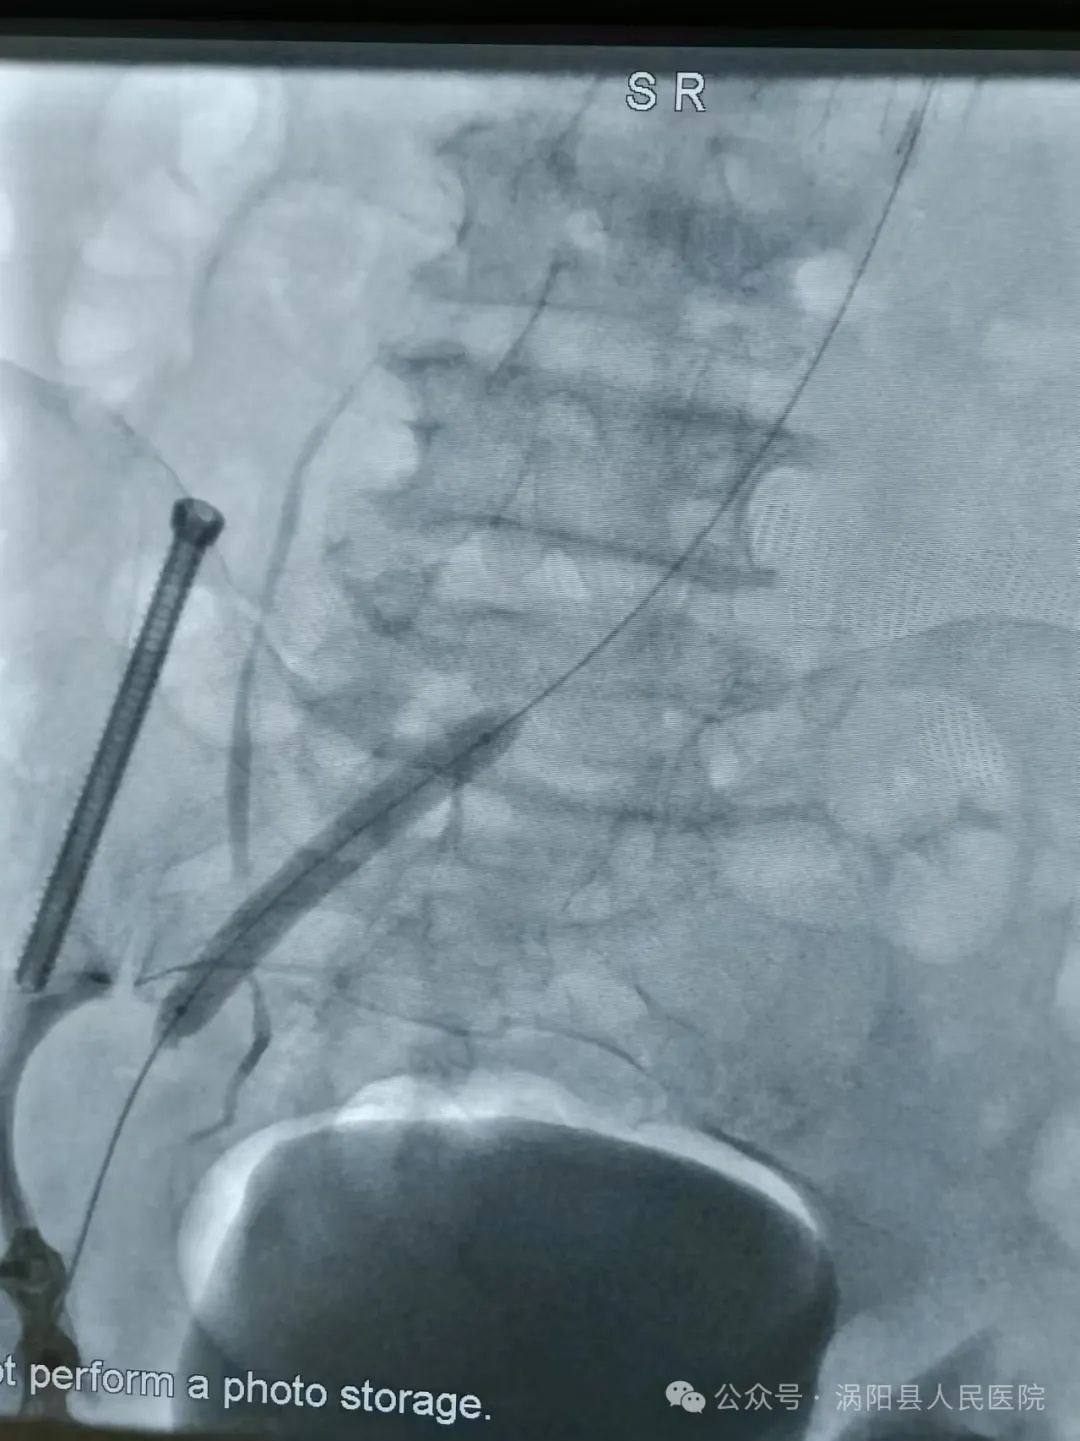

术中造影证实左下肢全肢型深静脉血栓形成

滤器置入

放置溶栓导管

导管直接接触溶栓(Catheter-Directed Thrombolysis, CDT),目前是各种指南推荐级别较高的一种DVT(深静脉血栓形成)的治疗手段,溶栓药物经过溶栓导管的侧孔直接进入血栓的内部,直接接触血凝块,溶栓效果良好。